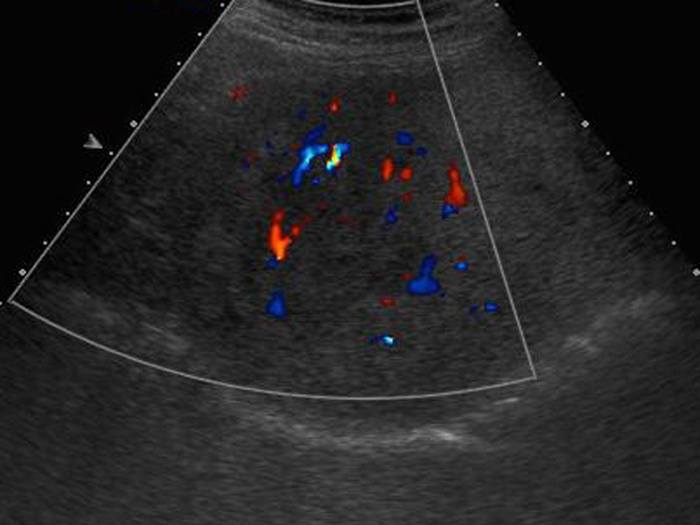

Sán lá gan

» Thông tin: Nam giới – 52 tuổi.

» Lâm sàng: Kiểm tra sức khỏe.